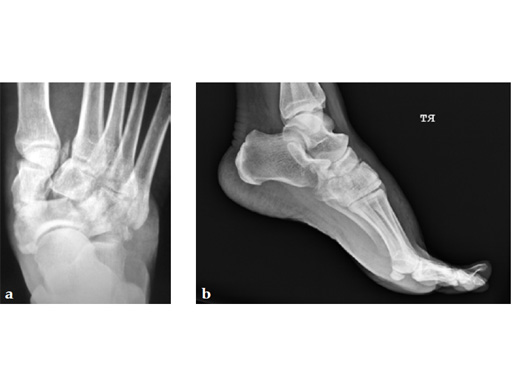

A 38-year-old man fell from a 7-foot height while at work. The patient was seen at an urgent care facility and diagnosed with an ankle sprain. He was placed in a stirrup brace and instructed to bear weight as tolerated.

After 4 months the patient presented for a second opinion. His complaint was pain to the lateral column and subtalar joint. The preoperative lateral x-ray is notable for a malunited talar neck fracture with subluxation of the subtalar joint. The disproportion of the medial and lateral columns and a cavovarus position of the foot are seen on both the AP and lateral views. The degenerative changes at both the talonavicular and subtalar joints are significant.